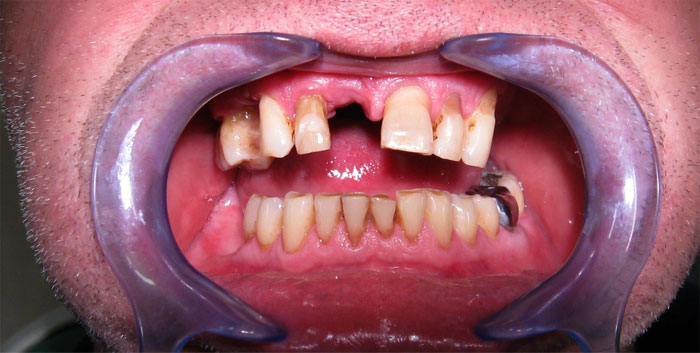

CAS N°2 Bridges sur 6 implants dentaires DIO mâchoire supérieure. La 1ère étape à consisté à extraire les 7 dents restantes et à poser une prothèse provisoire amovible. Quelques mois plus tard pose de 6 implants DIO et 3 mois plus tard la pose du bridge sur implant.